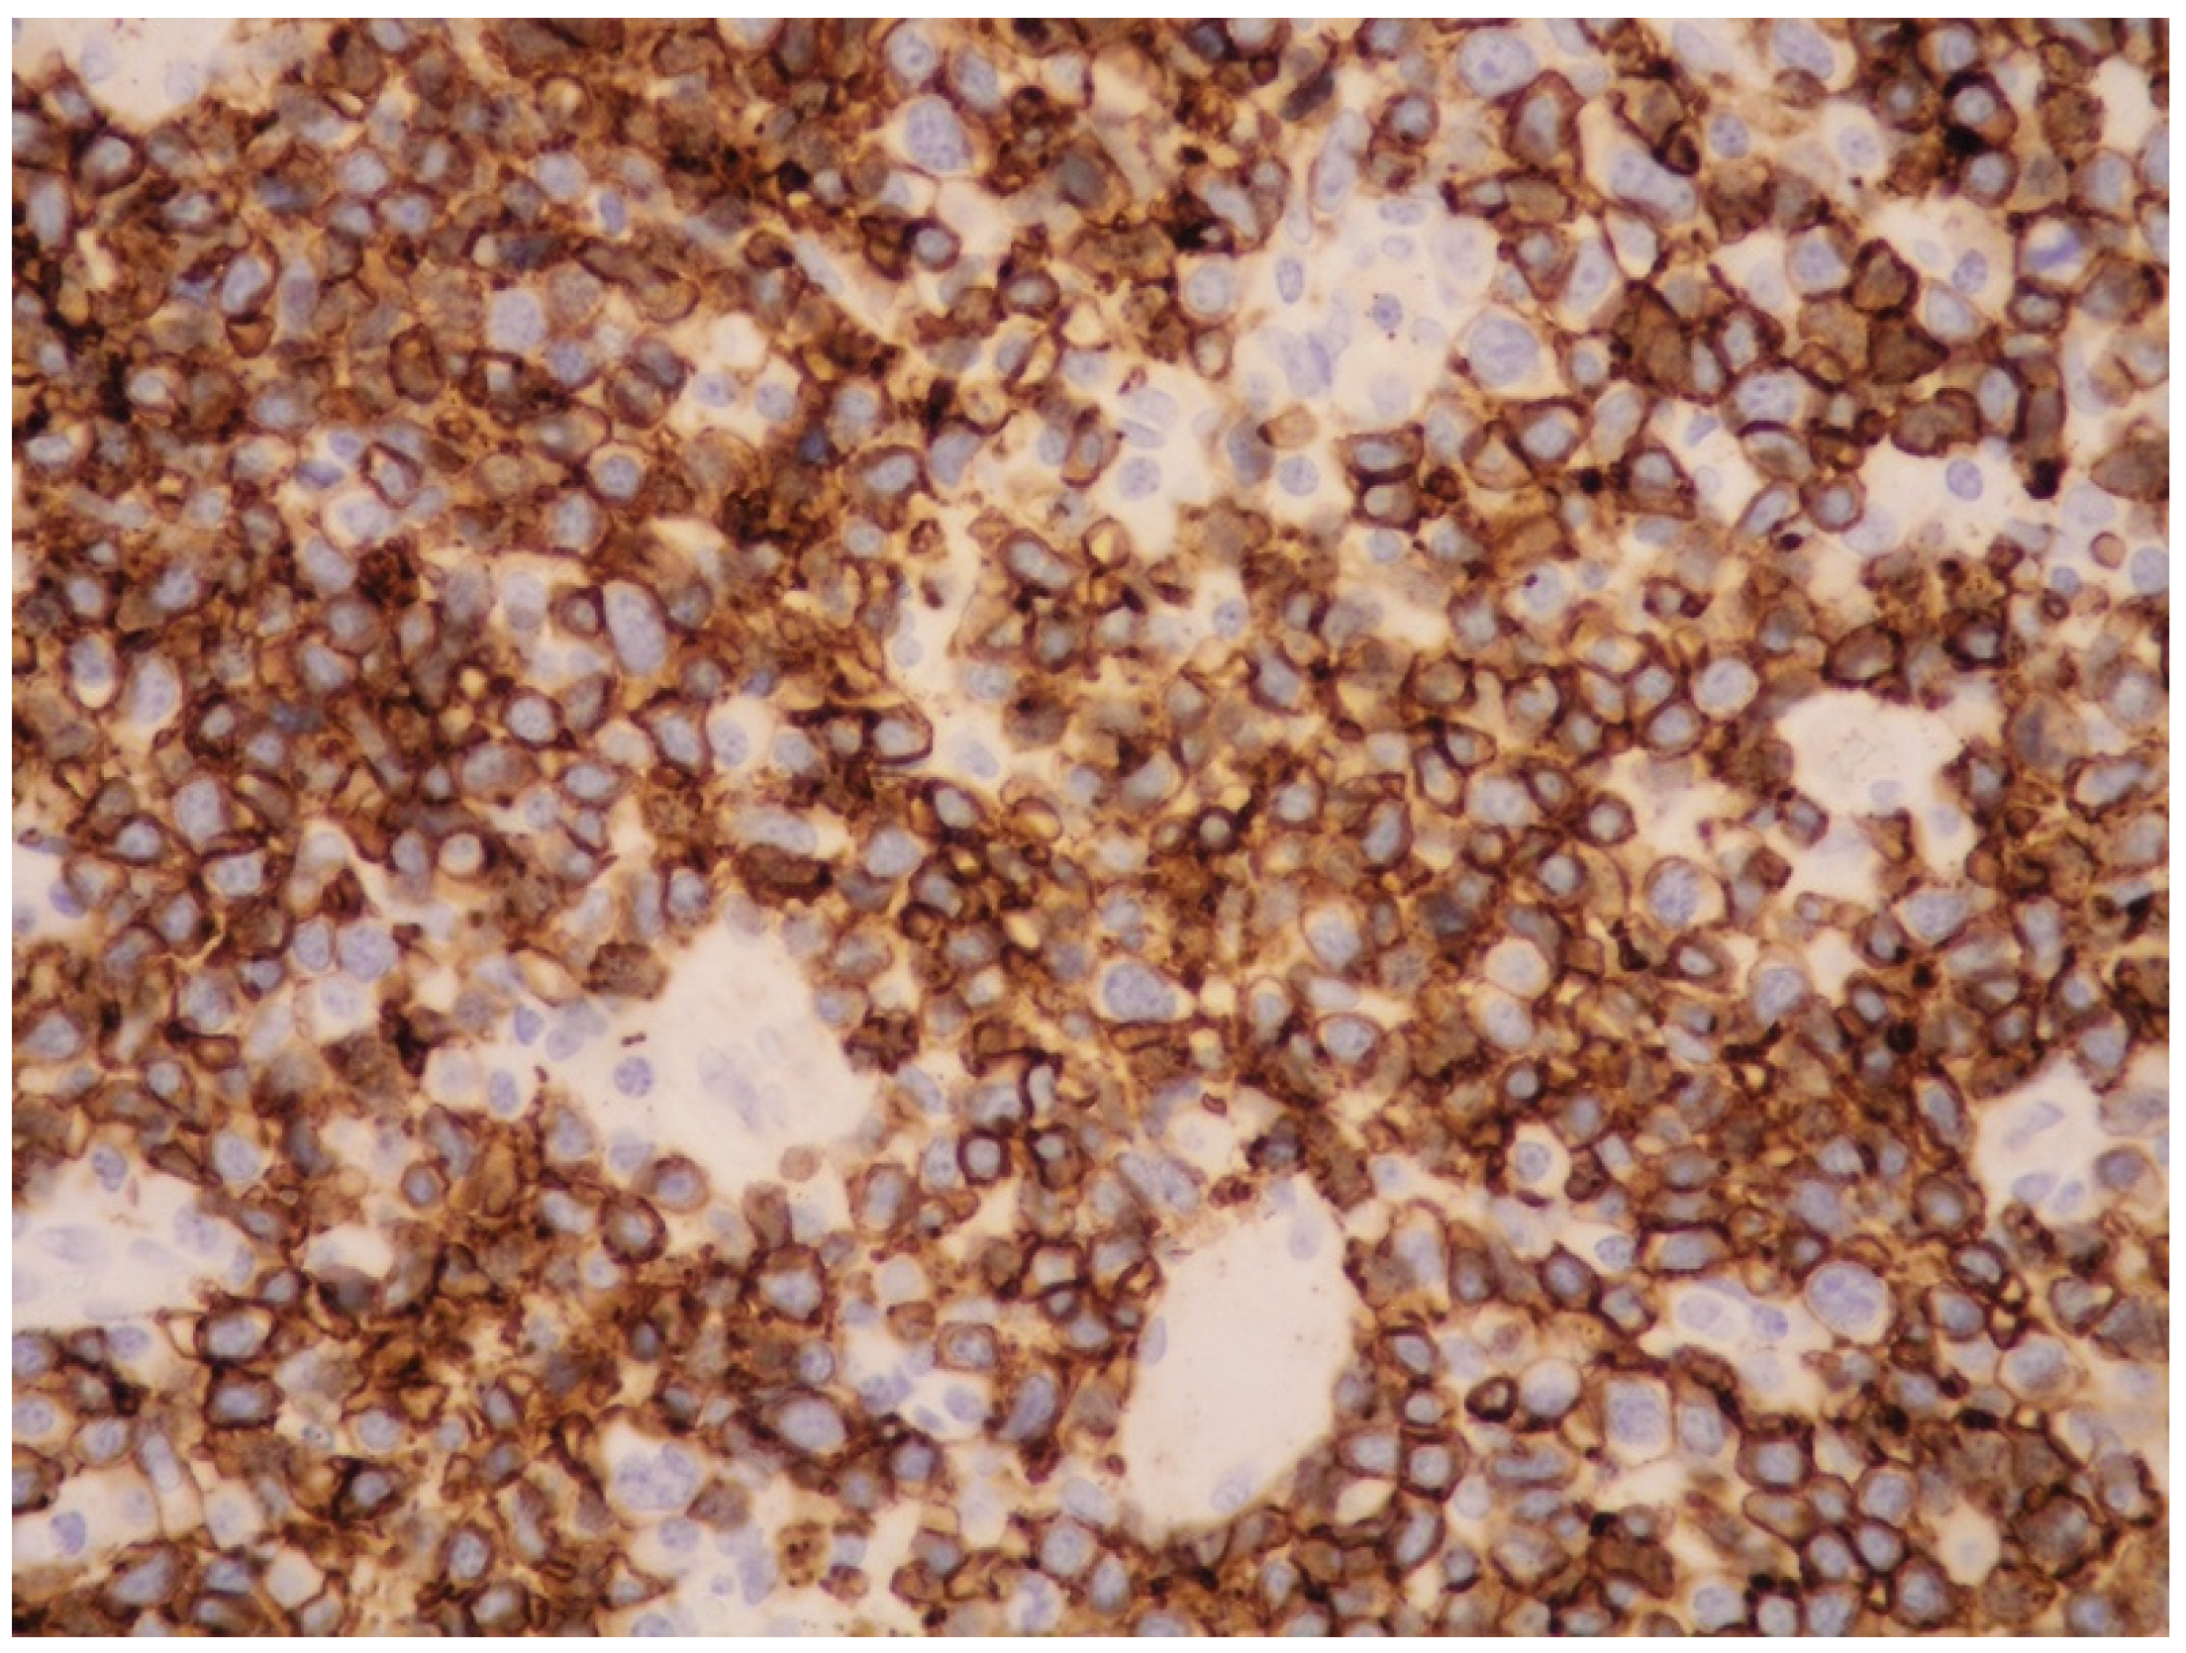

6.4.2. Histology and Immunophenotypic Features